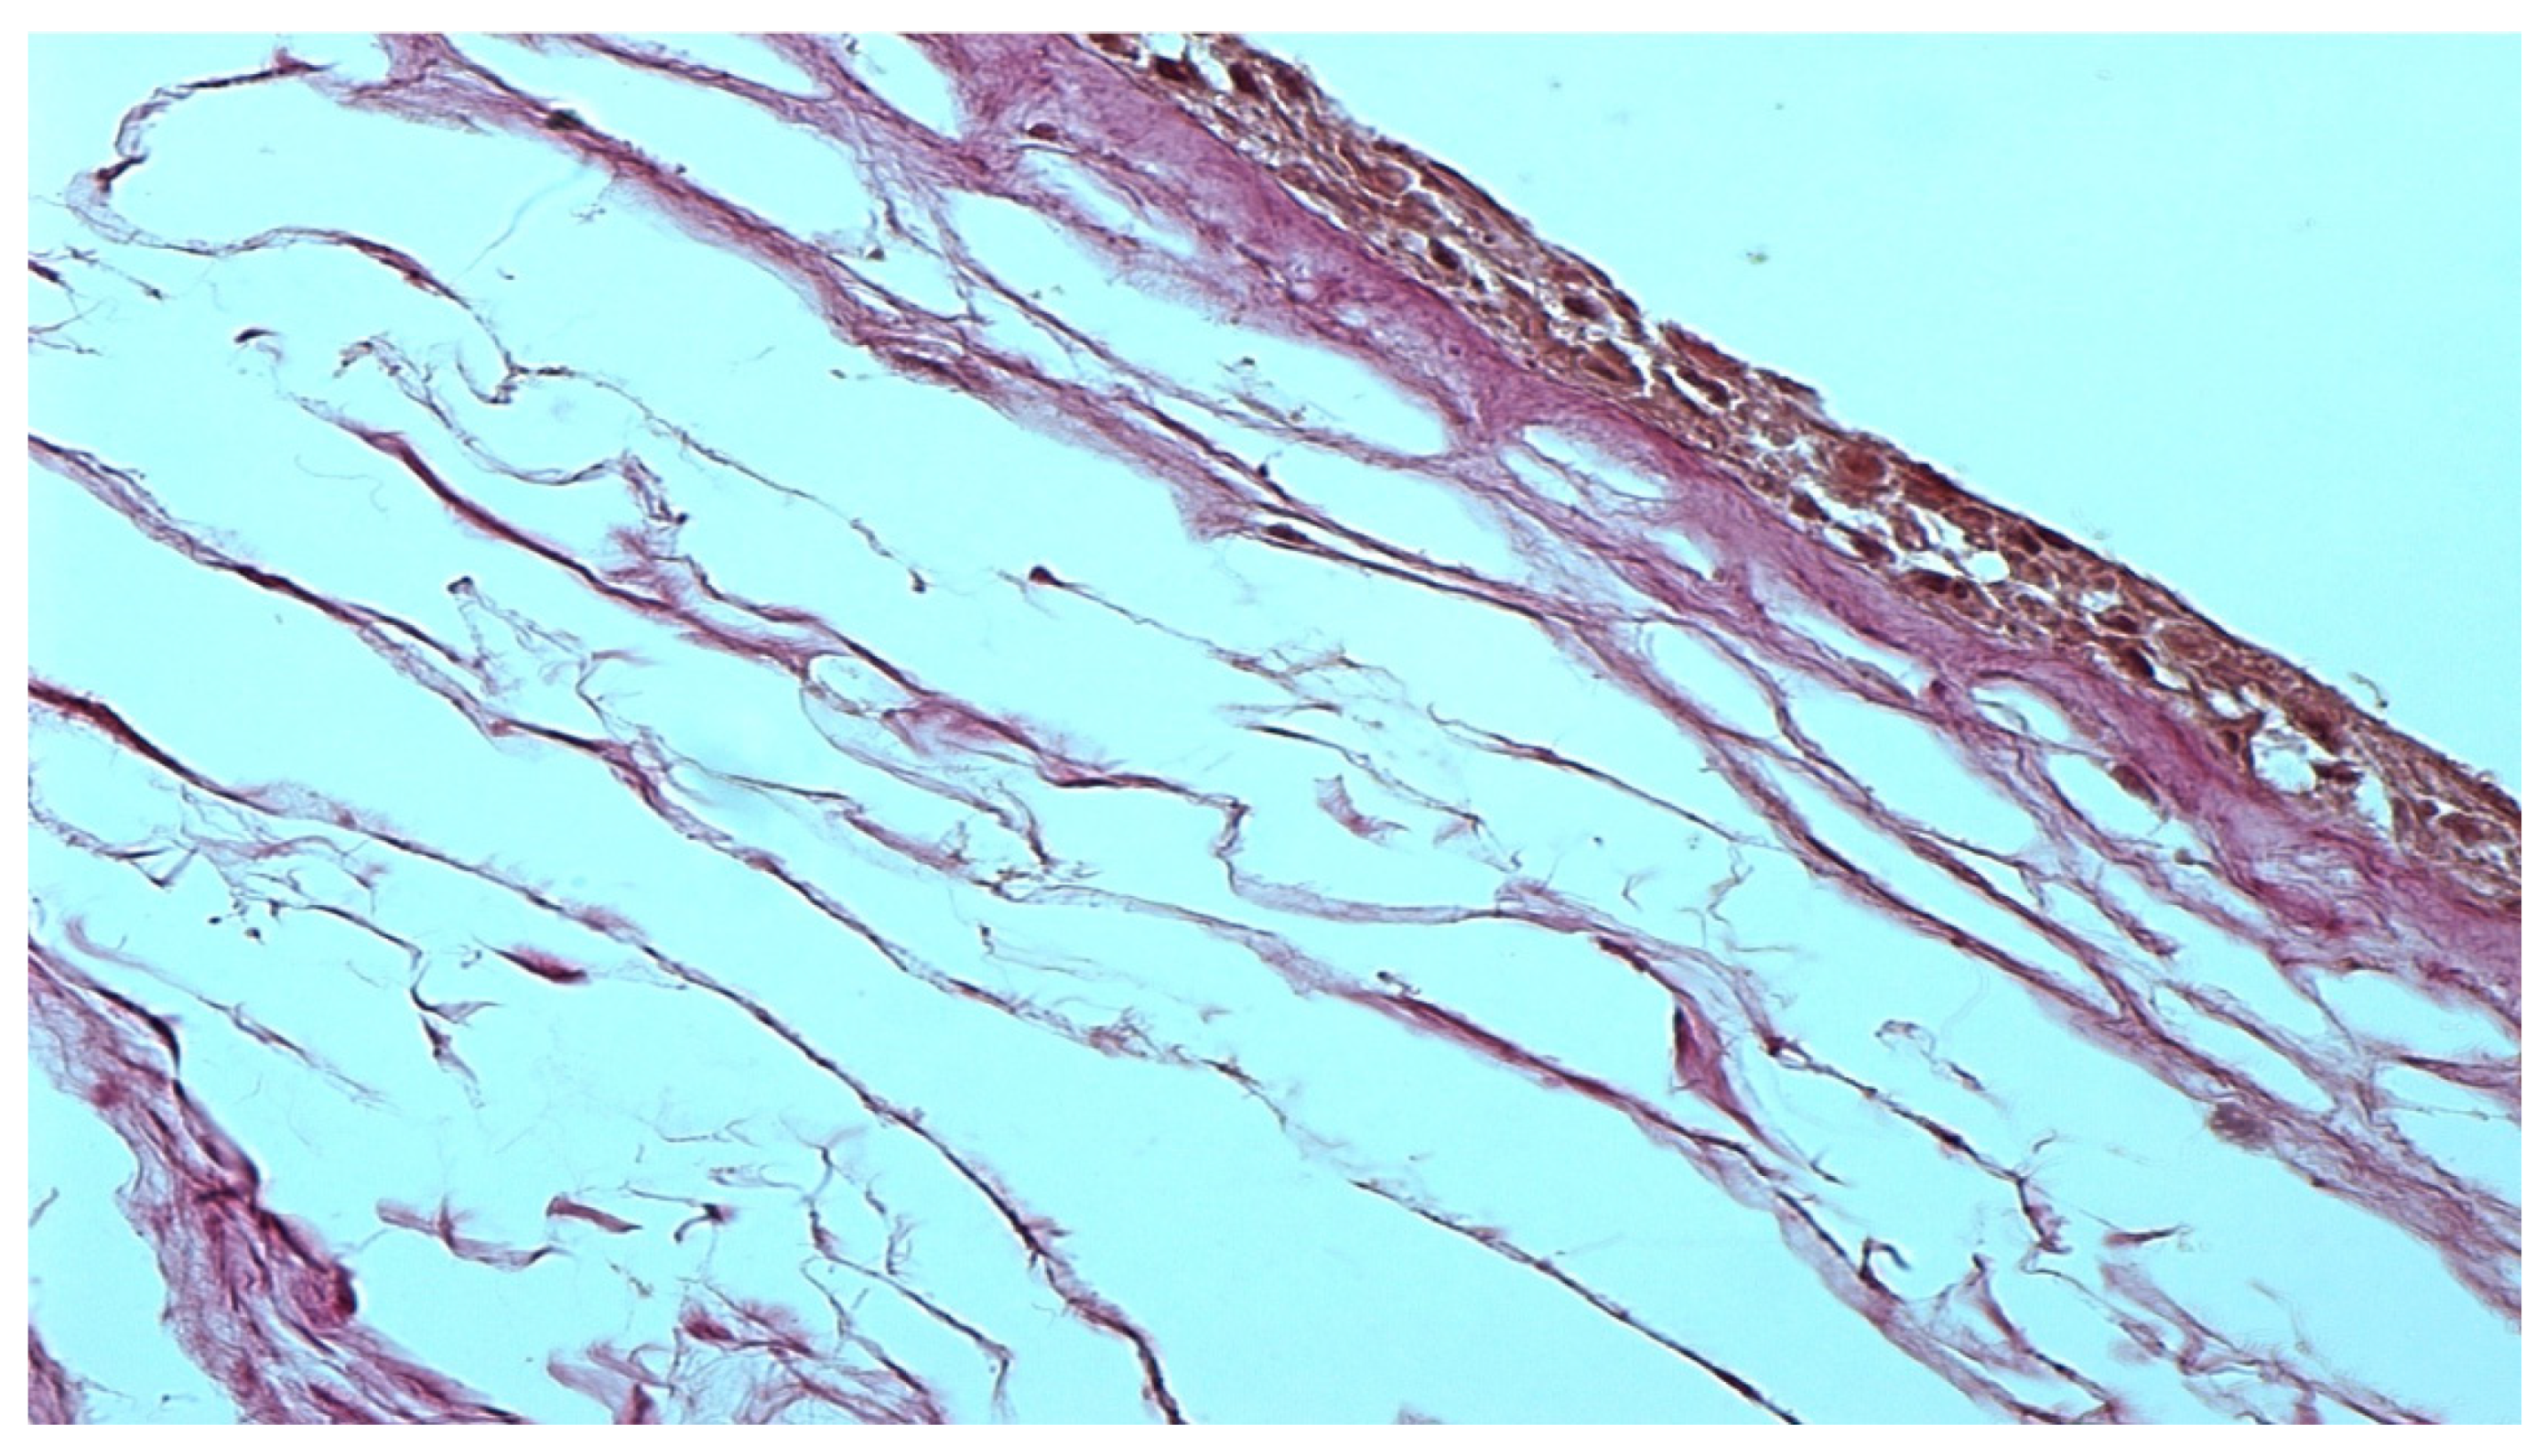

The morphological preparation of the native amniotic membrane presented in Figure 1 demonstrates a completely intact epithelial layer with viable cells and many pinocytic vesicles (indicated by an arrow in Figure 1). A compact layer consisting of densely intertwined collagen fibers is adjacent to the basal membrane, and the fibroblast layer is loose with fibroblasts located in the interweaving of reticular fibers. The spongy layer is represented by delicate, randomly intertwined reticular fibers.

Figure 1. Native amniotic membrane preparation. Stained with picrofuchsin. −×400.